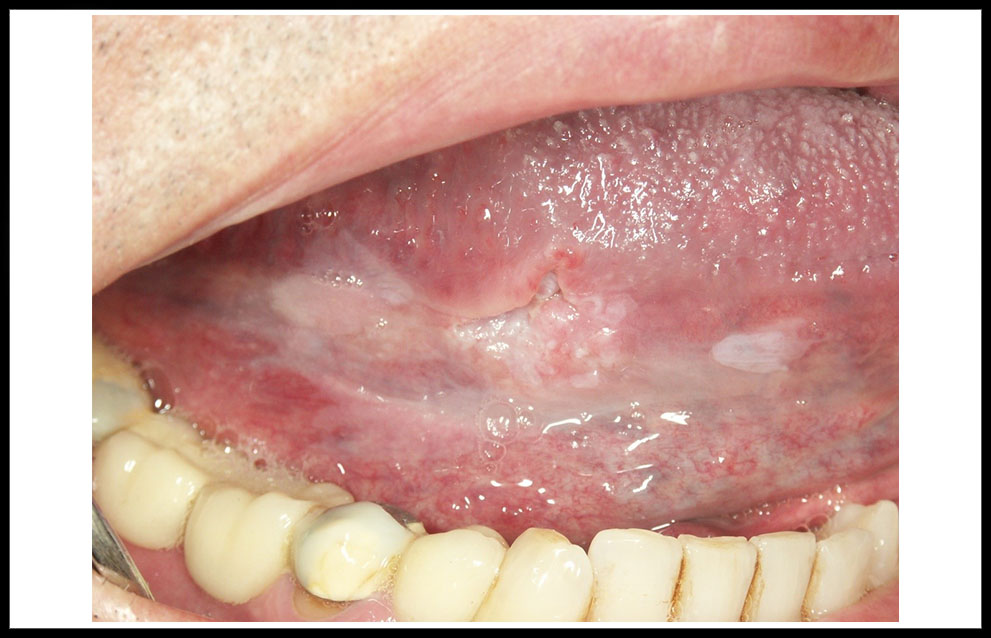

La leucoplasia oral aparecen con una frecuencia algo superior en hombres (6/4), en edades comprendidas entre los 40 y 60 años. Desde el punto de vista clínico, una clasificación clásica considera 4 tipos esenciales der leucoplasia que tienen una correspondencia pronóstica. Las formas homogéneas son placas homogéneamente blancas que pueden presentar pliegues más o menos profundos (figura 1). Las leucoplasias no homogéneas integran a su vez tres subtipos: Las denominadas leucoplasia nodulares retrocomisurales, frecuentemente infectadas por Candida albicans (figura 2); las eritrolecucoplasias, que asocian áreas blancas y rojas (figura 3); y las leucoplasia verrugosas, que presentan una superficie verrugosa con aspecto parecido al de una coliflor (figura 4). Un tipo clínico especial, no incluido en la clasificación precedente, está constituido por la leucoplasia verrugosa proliferativa. Se trata de una lesión blanca que aparece en mujeres de edad avanzada, no fumadoras ni bebedoras, inicialmente limitada, aunque progresivamente expansiva afectando a zonas amplias de la mucosa oral, especialmente la encía y el paladar, y asociada a un riesgo muy elevado de desarrollo tumoral múltiple de cavidad oral (figura 5).

Figura 3. eritroleucoplasia del dorso de la lengua. Obsérvese la asociación de áreas rojas y blancas.